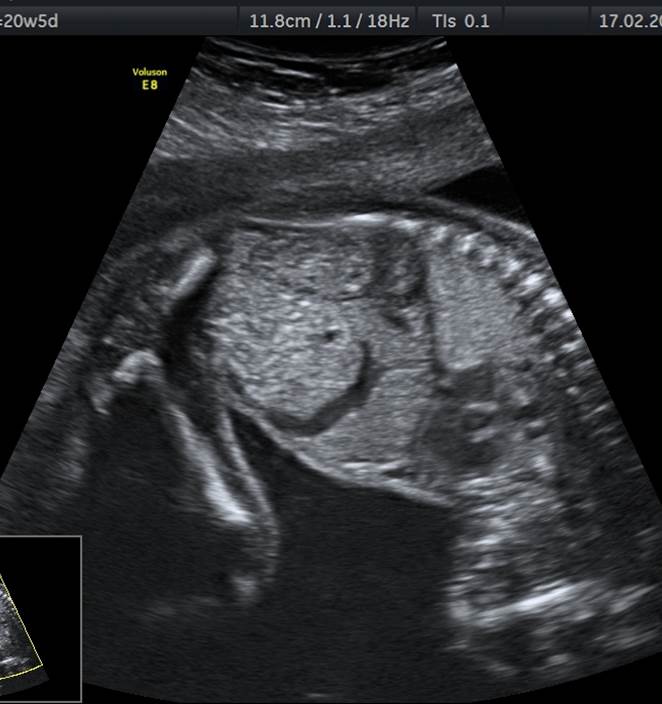

Проанализируйте изображения и видео-клип плода женского пола в 20 недель, установите диагноз и дальнейшую тактику ведения беременности

- Ниже полюса правой почки определяется округлое образование с анэхогенным содержимым. Мочевой пузырь выглядит нормально. Кишечник выглядит типично для данного срока беременности, петли его не расширены.

- Дифференциально-диагностический ряд включает кисту почки, кисту яичника, мезентериальную кисту.

- Учитывая срок беременности, а так же расположение сразу под почкой, киста яичника является наименее вероятным диагнозом (обычно кисты яичника манифестируют в 3 триместре беременности и располагаются ближе к мочевому пузырю, а не к почке).

- На видео-клипе не прослеживается связь образования с почкой, поэтому диагноз простая киста почки тоже отвергается.

- Правильный диагноз – мезентериальная киста. Прогноз благоприятный, никаких дополнительных обследований для этого плода не требуется.